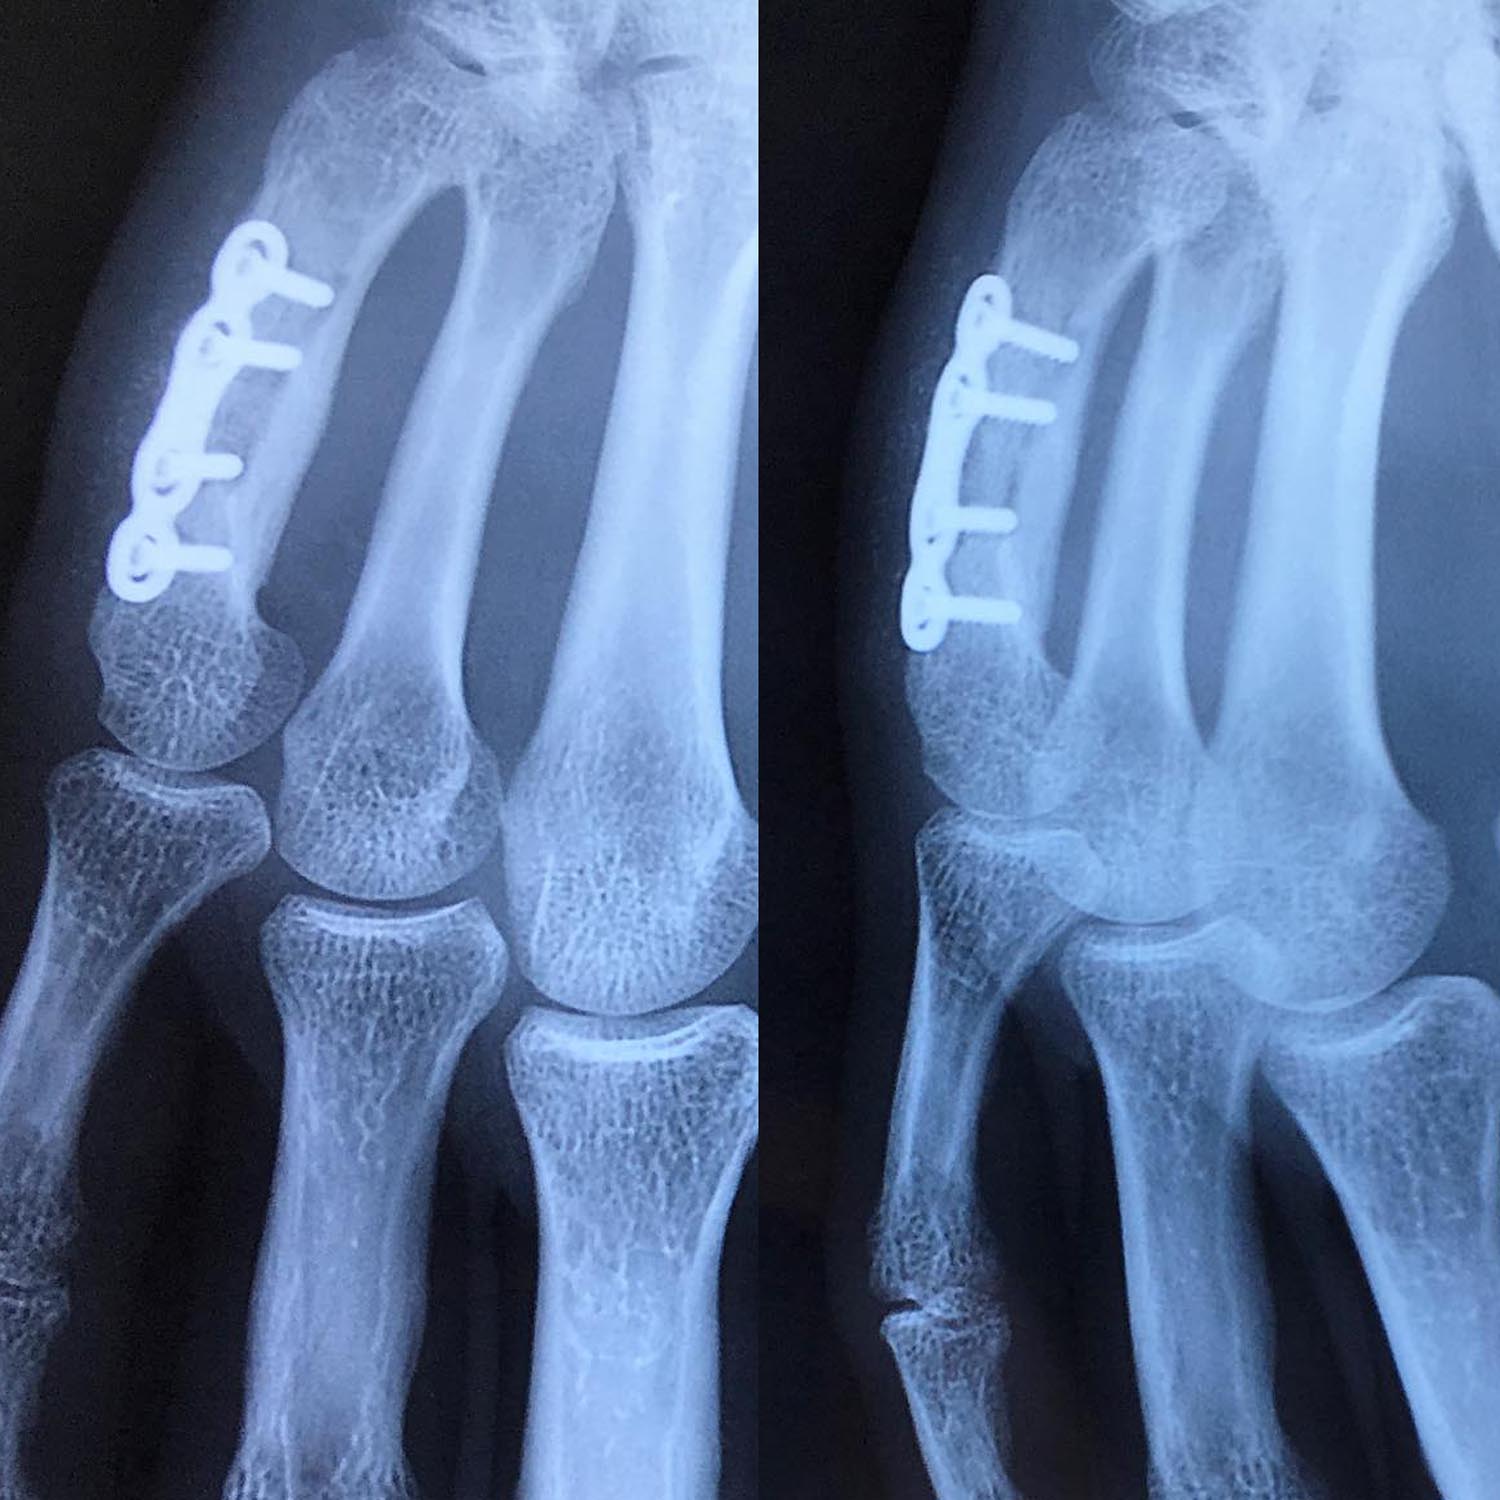

Fractures des 2ème et 3ème métacarpiens

Ostéosynthèse du 3ème métacarpien par vissage direct et du 2ème métacarpien par plaque vissée